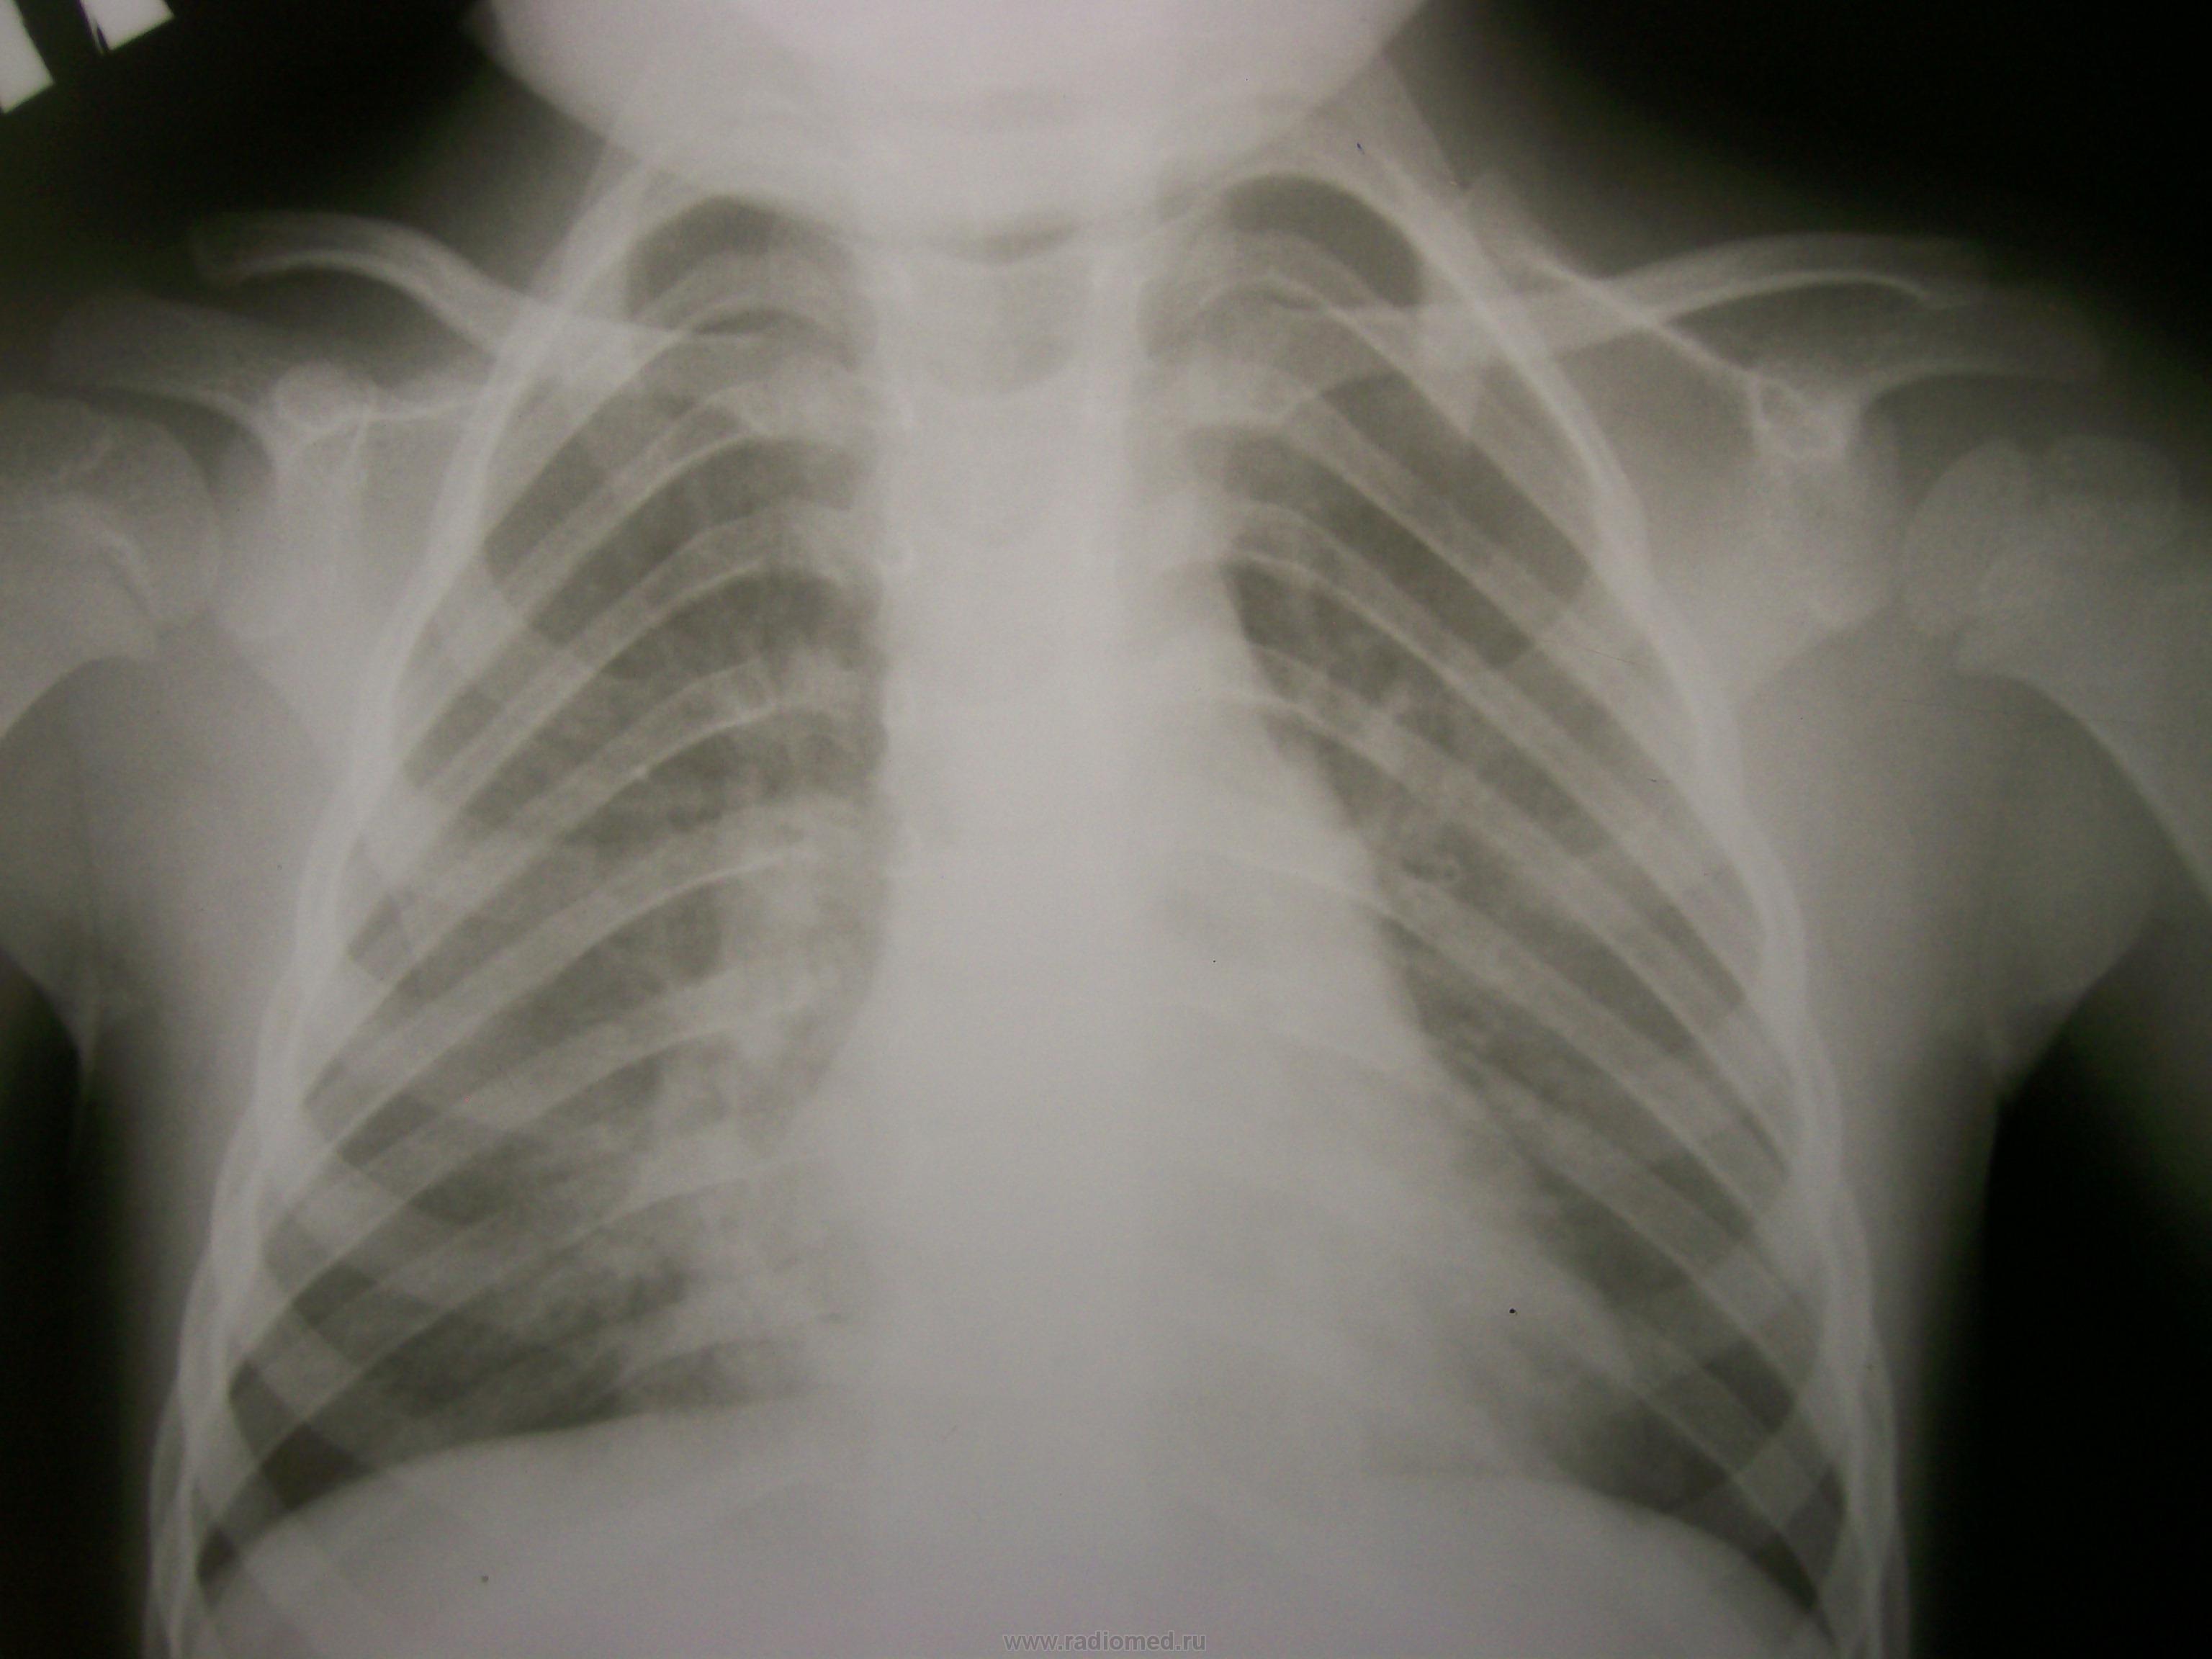

Ребенку сделали контроль после лечения антибиотиками. (Делали диаскин-тест - результат отрицательный.)

Что скажете, коллеги?

А динамика-то положительная.Среднедолевая,наверное,была.

На прямом снимке справа сохраняется расширение корня, "замазанность" кардио-диафрагмального угла. R-динамику продолжить, учитывая анамнез.

Я тоже указала на положительную динамику и сохраняющуюся сниженную воздушность нижних отделов справа. Боюсь, что R-динамику я уже не увижу. Самочувствие малыша улучшилось и он благополучно отправился домой. В сентябре плановое обследование в области.

Рентгендинамика очень хорошая. Я бы, наверное, указал в заключении - R-динамика через месяц. Главное - указать, а потом сделать. Можно и в областном центре, и чуть позже.